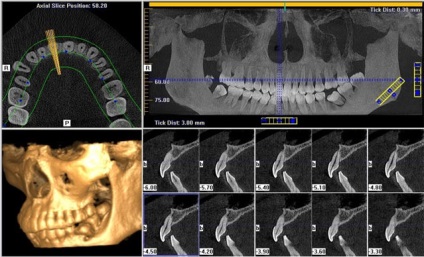

Mi fogászati tomográfia

Végrehajtása során bármilyen típusú CT elvet használja a röntgen sugarak különböző vezetőképességű test különböző szöveteiben :. üregek, csontok, izmok, szalagok, stb Ebben az esetben a sugarak áthatolnak minden szövetet a test és a csapdába esett egy speciális érzékelő. Miután egy sor köteg képeket a számítógép beépített komputer tomográfiás 3D modellt.

Röntgendiffrakciós módszer nem biztosítja az összes előnyöket, amelyeket lehet egy olyan eljárás biztosítása a modern komputertomográfiás. CT fogak lehetővé teszi, hogy vizsgálja meg a különböző funkciókat a fogak állkapocs anatómiája: a szerkezet a fogak és a csatorna állapotát az állkapocs csont.

CT eredmények nélkülözhetetlenek ortopédiai, gyermekgyógyászati fogorvosok, fogszabályzó, sebészek. Például a legpontosabb bármelyikének gyártására műfogsor orvos gyakran információt a pontos méreteit a mandibula anatómiai tájékozódási pont árnyalatok maximum fogazás. Csak ebben az esetben a protézis lehet előállítani a maximális kényelmet a beteg számára.

Modern eredmények a fogászat, és előírja az ultra-modern diagnosztikai módszerek. Azaz ez a módszer CT fogak. Számos szakértő hívja fel a modern tomográfiás vizsgálat a kifejezés «3D CT-vizsgálat.”

3D képalkotó módszer tekinthető jelenleg az egyik legjobb diagnosztikai módszerek. Leggyakrabban, fogorvosok használ spirál-CT berendezés egy kúpos sugárnyaláb. Ebben a speciális programot értelmezi az eredményeket, és a késztermék panoráma kép az orális állkapcsát.

- háromdimenziós képet feltárja az összes árnyalatok az eltéréseket az állam a fogak és az íny, hogy válassza ki a legmegfelelőbb kezelést.

- Amikor létrehozó patológia sverhtochen szkenner azonosítani a legkisebb árnyalatok: felbontás, lokalizáció, mértéke a forgalmazás, és mások.

- Képes megváltoztatni a skála lehetővé teszi számunkra, hogy fontolja meg olyan formában, minden szegmensében a fogak vagy az állkapocs.